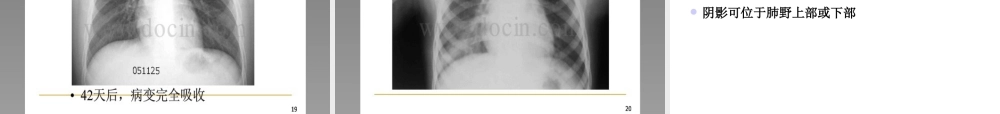

不明原因肺炎病例监测、排查和管理方案呼吸内科关键概念传染性非典型肺炎(SARS)人感染高致病性禽流感(人禽流感)均以肺炎为主要临床表现的急性呼吸道传染病是是《《中华人民共和国传染病防治法中华人民共和国传染病防治法》》规定的乙类传染病,按甲规定的乙类传染病,按甲类传染病采取预防和控制措施。类传染病采取预防和控制措施。不明原因肺炎流行病学人群分布年龄分布最小1岁至3个月,最大53岁以中青年为主性别分布男女无显著差别职业分布有接触史医护人员发病率占42%家庭聚集性流行病学传播途径空气飞沫通过接触呼吸道分泌物的手传播人群易感性普遍易感以中青年为主流行病学流行方式散发家庭聚集性暴发流行病因探寻现状可能病因细菌支原体、衣原体病毒真菌但迄今为止仍未确定不明原因肺炎发热(腋下体温≥38℃)具有肺炎的影像学特征发病早期白细胞总数降低或正常,或淋巴细胞分类计数减少;经规范抗菌药物治疗3-5天,病情无明显改善或呈进行性加重同时具备,且不能明确诊断为其它疾病的肺炎病例可诊断为不明原因肺炎如何排查其他肺炎认识不明原因肺炎,首先必须认识普通肺炎社区获得性肺炎社区获得性肺炎是指在医院外罹患的感染性肺实质(含广义的肺间质)炎症,包括具有明确潜伏期的病原体感染而在入院后平均潜伏期内发生的肺炎CAP的临床诊断依据1.新近出现的咳嗽、咳痰或原有呼吸道疾病症状加重,并出现脓性痰,伴或不伴胸痛2.发热3.肺实变体征和(或)闻及湿性啰音4.WBC>10×109/L或<4×109/L,伴或不伴细胞核左移5.胸部X线检查显示片状、斑片状浸润性阴影或间质性改变,伴或不伴胸腔积液CAP的临床诊断依据以上1~4项中任何1项加第5项,并除外肺结核、肺部肿瘤、非感染性肺间质性疾病、肺水肿、肺不张、肺栓塞、肺嗜酸性粒细胞浸润症及肺血管炎等后,可建立临床诊断。社区感染特点半数以上的临床肺炎病原体不能明确。社区获得性肺炎病原体检出率仅为48.5%。因此仍有部分病例靠临床诊断性治疗推断病原体可能;抗生素耐药率上升;非典型肺炎及阴性杆菌肺炎发病日益增加,传染性强;免疫损害宿主增加。病毒、真菌、结核及混合感染发病增加;不明原因肺炎的病因学复杂—恶性传染病、常见病原体引起的不典型肺炎;社区获得性肺炎病原体肺炎链球菌、流感嗜血杆菌、卡他莫拉菌—典型病原体肺炎支原体、肺炎衣原体、军团菌—非典型肺炎,呼吸道传染,家庭和医院聚集现象,有比较强的传染力SARS流行及人禽流感疫情使我们对病毒性肺炎日益重...